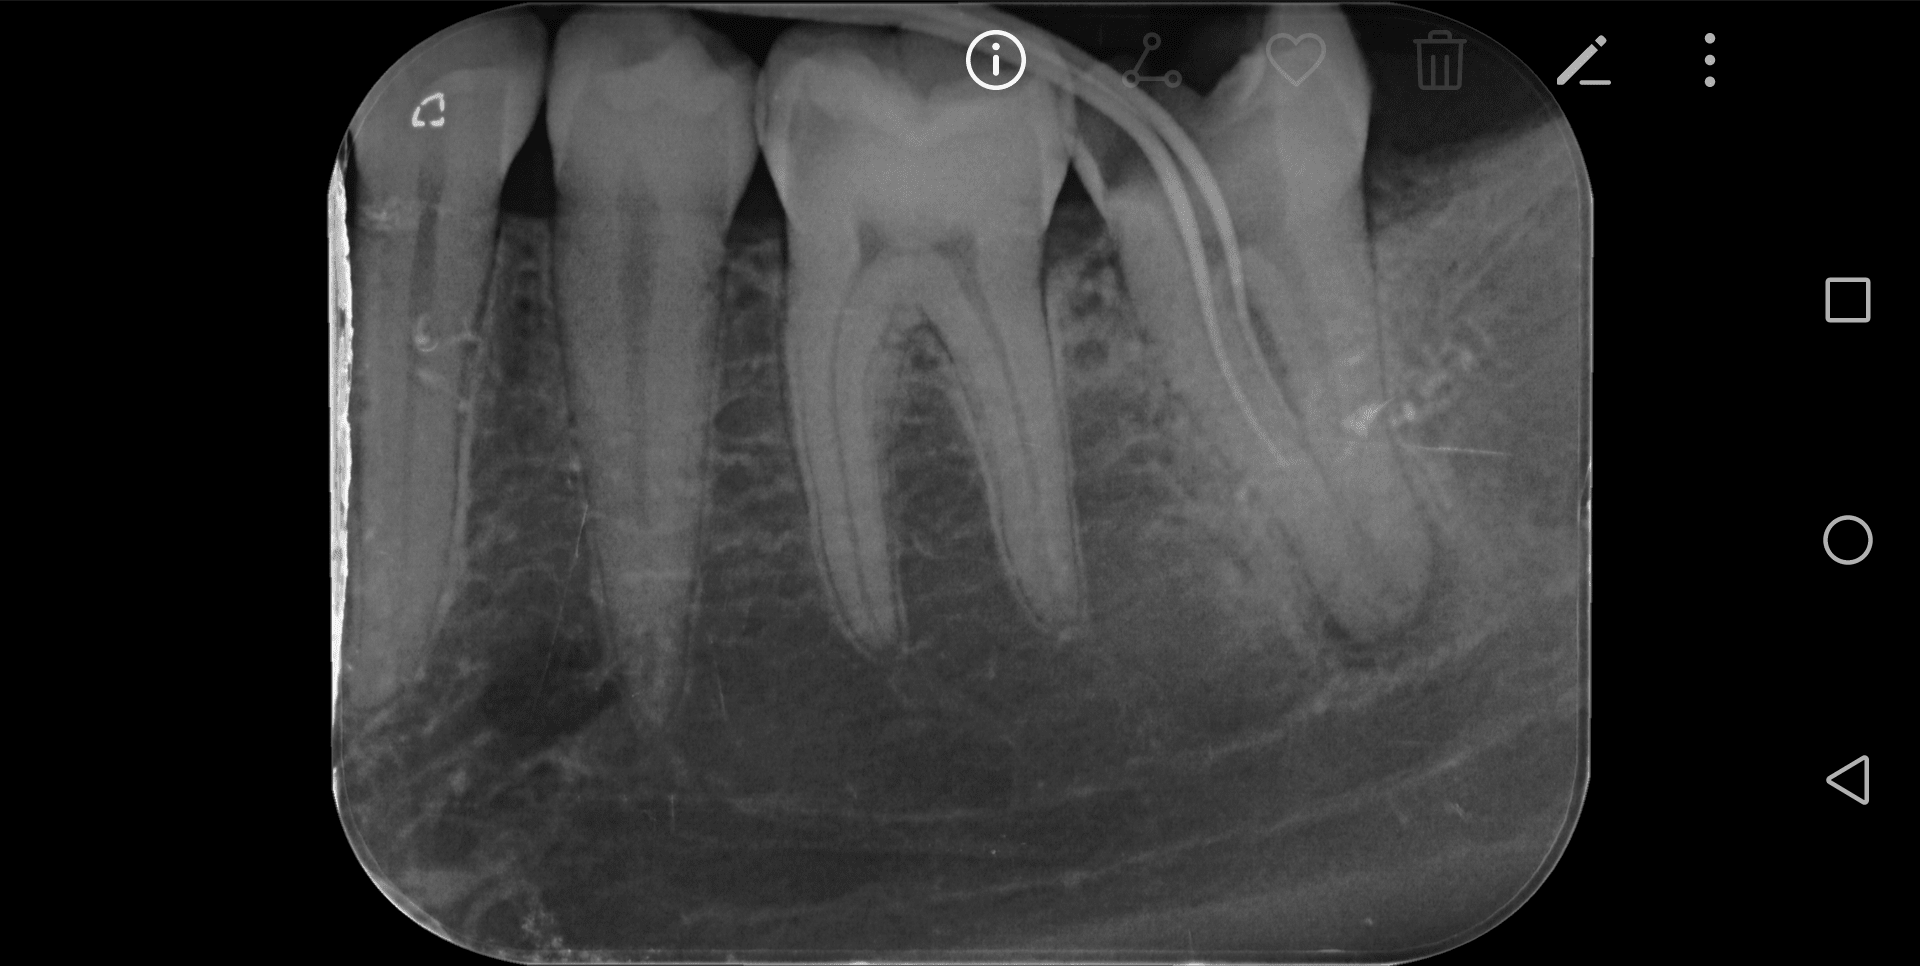

Diagnostic : Parodontite chronique apicale en phase aigue, il y a une semaine. Anesthesie impossible à ce moment la, mise sous AB depuis 5 jours. Au vu de la radio pre-op je considère le TR comme potentiellement compliqué.

Un gros canal Distal très excentré en vestibulaire est trouvé, ainsi qu'un fin canal MV relié au canal distal par un isthme peu profond. Je trouve également un fin canal ML. Les deux canaux mésiaux se situent bien en mesial, sur la même ligne parallèle au bord mesial et séparés de 1mm.

Parage canalaire des trois canaux à la LK 8/10/15/20 sur LT initial de 19mm et irrigation. ouverture du foramen avec gates. Aucun saignement.

Je fais une radio per-op avec deux cônes de gutta fins de diamètre 20 4% dans les deux canaux mésiaux et … surprise…

Qu'en pensez-vous ?

1/Mon ML correspond a un canal secondaire qui va du plancher pulpaire vers l'espace interdentaire ? Ou bien ML dans racine que je ne vois pas (je ferai des radios excentré prochaine fois)?

2/Comment obturer si petit canal secondaire vers espace interradiculaire ? gutta? MTA ?

merci pour vos réponses, Pour la perf, je ne pense pas… D'ailleurs sur la pré-op on semble voir quelque chose à l'endroit de ma future pseudo perf..?

@bagheerra : J'ai édité mon message puisque je me suis trompé dans ma question 1/, je parlais du ML et non du DV. Les deux cônes sont dans les mesiaux comme indiqué.

Je suis assez sur que ce n'ai pas une perf, donc si localisateur sonne tôt, canal secondaire partant de la chambre vers espace inter radiculaire ? Dans ce cas la je n'ai que deux canaux, un MV et un Distal excentré en vestibulaire.

Si je regarde le plancher de la chambre pulpaire (couple transversale), mon C est relativement peu bombé en forme et va du MV classique au distal excentré en vestibulaire. Le dos du C est vers vestibulaire. N'es-ce pas curieux au vu de la radio pre-op ou l'on voit deux racines mesiale et distal séparées ? Ou bien le C est vraiment très peu profond comme j'en ai l'impression.

-canal secondaire du plancher vers l'espace inter radiculaire ne vous parait pas plausible ? au contraire plutôt une perf

-perf soit situé en MV faite lors de l'exploration du C, alors que le MV n'est pas présent. (uniquement le D et ML)

-soit situé en ML et uniquement canal MV et D situés dans le C

Bon après lecture des réponses et réflexion, j'opte (j'espère); soit, le moins probable, pour un canal secondaire de la chambre vers l'espace inter radiculaire, soit, le plus probable pour une anatomie en C donnant l'impression que mon MV est en inter radiculaire (type TIB postée par BURNAX).

Je vais tabler sur une morphologie en c (5 à 7% des 2e molaires mandibulaires) et une imagerie à la "burnax". Le plancher pulpaire ressemble au cas posté par Bill. Un c vestibulaire de distal à mv et un canal individualisé en ml. Dans ce cas le mv peut apparaître dans la furcation à la radio...